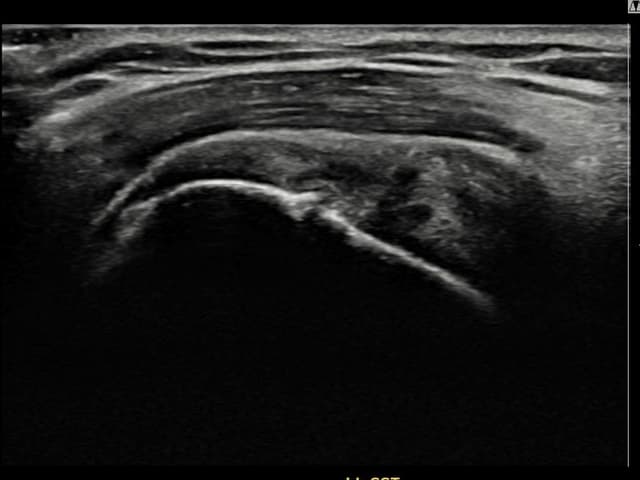

左侧 冈上肌腱 石灰化肌腱炎

9mm × 7mm